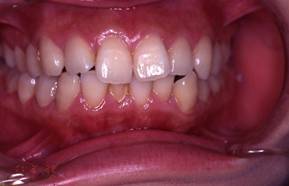

上顎前突+叢生 抜歯矯正(治療期間1年)

治療前、特に上の歯並びに問題がありました

奥歯のかみ合わせもよくありません

治療後、正中線も揃いました

小臼歯を抜歯しました

きちんと噛んでいます